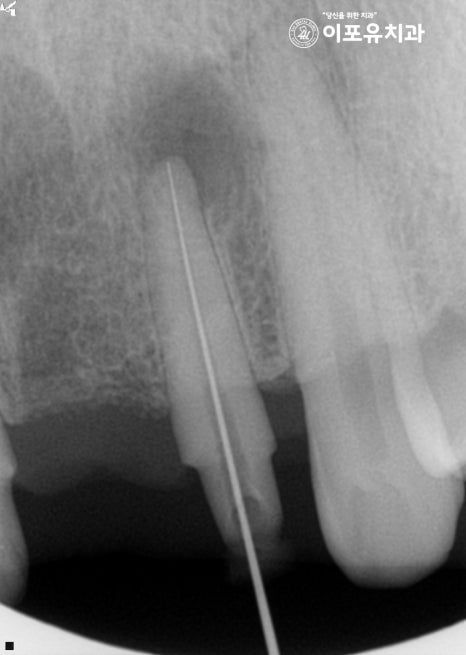

꾸준한 추적 관찰을 통해 확실하게 사라졌는지

확인을 하는 것이 좋은 방법이죠.

병소의 크기를 추적 관찰하여

재발의 확률은 없는지, 증상이 나아지고 있는지

꼼꼼하게 확인을 도운 뒤 전치부는 임시 보철을 씌워

좀 더 지켜보기로 하였으며,

작은 어금니는 지르코니아 크라운을 씌워

과정을 마칠 수 있었습니다^^